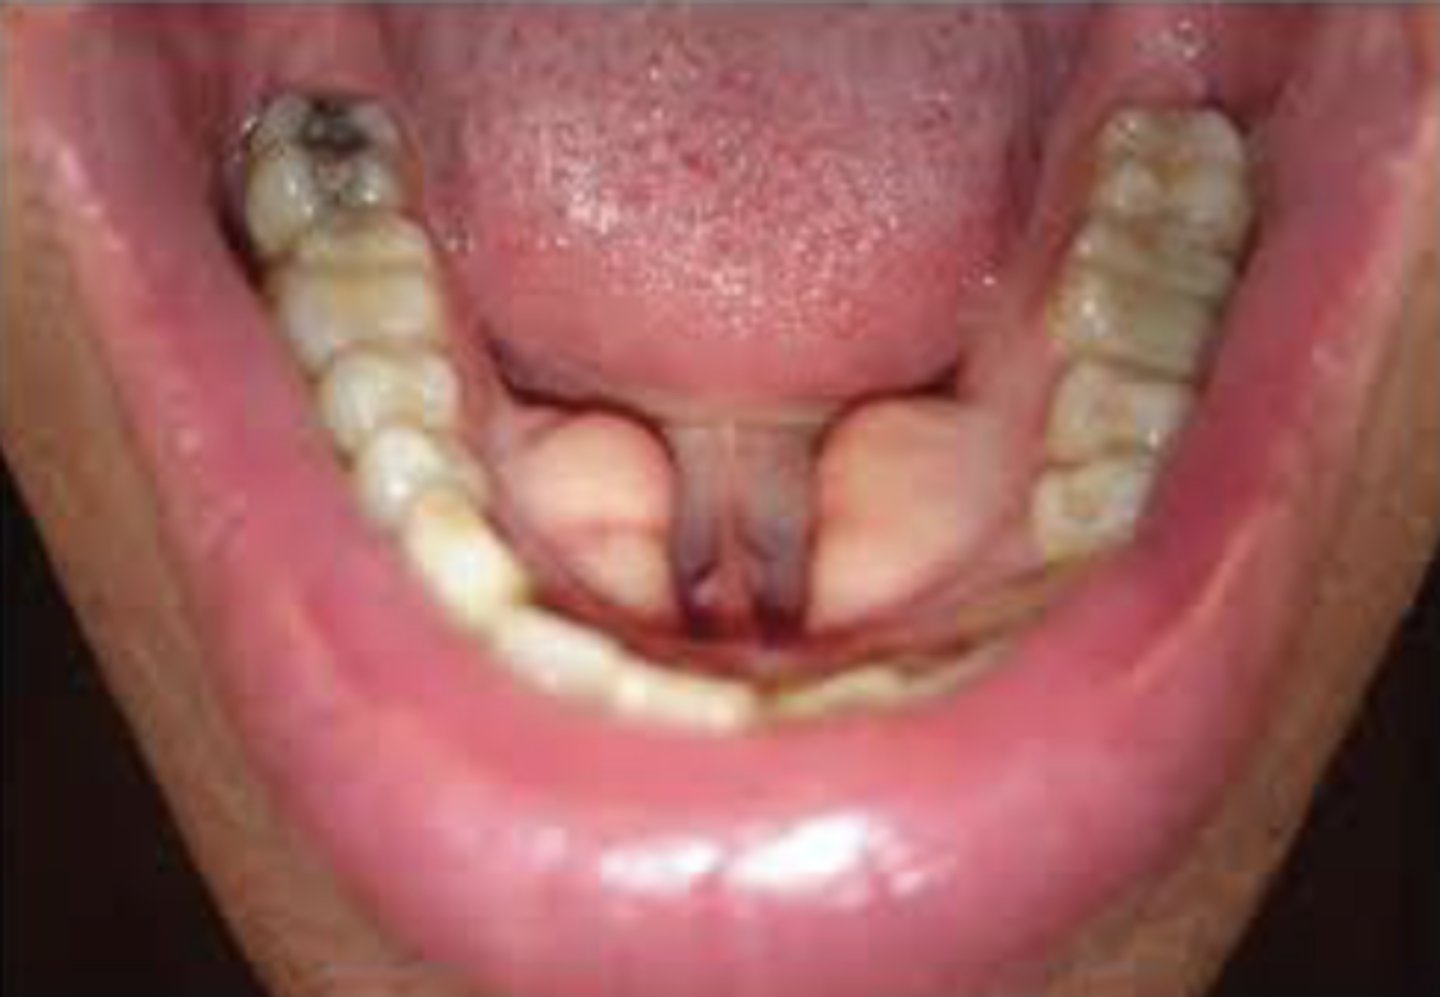

What is fusion?

Two tooth buds fuse to form one tooth

How many teeth are present in fusion cases?

One fewer than normal

What is gemination?

One tooth bud attempts to divide into two crowns

How many teeth are present in gemination cases?

Normal number of teeth